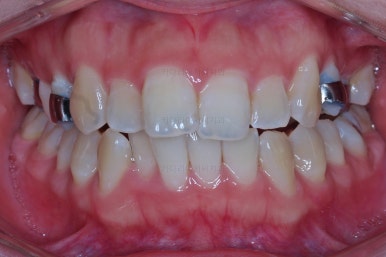

마찬가지로 초진 시 얼굴 모습입니다.

입 안의 모습에서는 보이지 않던 문제점이 바로 파악이 되실겁니다.

정면 모습에서 안면비대칭이 느껴집니다.

아래턱이 좌측으로 틀어져 있고요. 보통 턱이 틀어지는 방향으로 입술도 같이 끌려가기 때문에 입술이 기울어 있는 상태입니다.

단순히 입술만 기울어 있는 것은 아니고 치열도 같이 기울어 있는데요.

무슨 말씀이냐면, 머리 뼈라는 기준에 대해서 왼쪽 치열이 위로, 오른쪽 치열이 아래로 내려가 있어 전반적인 기울어짐을 보입니다.

따라서 이번 환자분은 턱끝 틀어짐-입술 기울어짐-치열 기울어짐이 모두 나타나는 상황이었습니다.